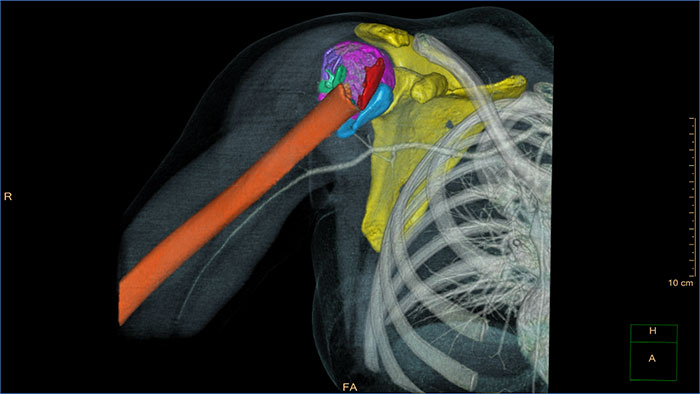

CT Acute MultiFunctional Review (AMFR)

One application for the assessment of selected anatomies

CT Acute MultiFunctional Review (AMFR) provides dedicated tools for findings detection, visualization and assessment of vessels, bones and spine anatomies in 2D and 3D CT images.

Benefits

- Automatic navigation-path for calculation of the spinal cord as well as automatic detection and labeling of spine vertebrae and discs.

- Bones segmentation using an interactive segmentation tool to create a workspace for virtual repositioning of individual bone segments.

- Provides segmentation, editing and measurement tools for vascular analysis.

- Predefined layouts per anatomical area: head, chest, abdomen, spine and extremities.